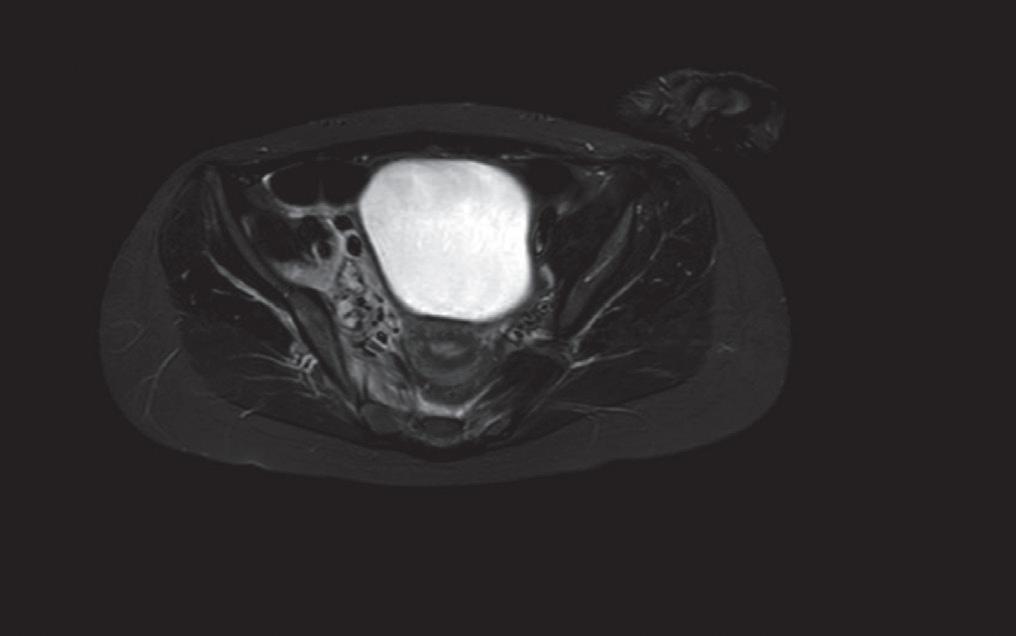

G., 16 anni, affetta da grave scoliosi idiopatica, giunge in Italia dalla Costa d’Avorio per eseguire correzione chirurgica di tale difetto. Dopo 9 giorni dall’intervento numerosi episodi emetici con addominalgia diffusa; non febbre, alcune evacuazioni diarroiche. All’arrivo in pronto soccorso: PV nella norma, paziente sofferente, pallida, diffusa dolenzia addominale, restante EO nei limiti. Agli esami ematici: GB 21.000/uL, N 91,4%, PCR 26,4 mg/dL; all’ecografia addominale distensione gastrica e intestinale a contenuto liquido. In seconda giornata, dopo iniziale miglioramento, ripresa dell’algia addominale con tre ulteriori episodi emetici. Nel sospetto di quadro occlusivo si eseguivano RX addome [Figura 5]: livelli idroaerei gastrici e in ipocondrio dx, in assenza di aria libera; TC addome [Figura 6]: marcata gastrectasia a contenuto fluido con dilatazione duodenale fino al Treitz. Si applicava sondino naso-gastrico con aspirazione di 400 ml di contenuto maleodorante; la successiva RX prime vie digerenti con m.d.c. confermava l’occlusione duodenale [Figura 7]. Alla laparotomia urgente, per evidenza di compressione ab estrinseco del duodeno da parte dell’arteria mesenterica superiore (AMS) [Figura 8], venivano eseguite resezione e anastomosi duodeno-digiunale. All’RX post-intervento con m.d.c. normale transito intestinale [Figura 9]. La causa del quadro occlusivo era data dalla sindrome del compasso aorto-mesenterico (SCAM) correlata alla recente artrodesi.

Nel caso in esame la rettilineizzazione della colonna ha determinato un “effetto pinza” sul duodeno. Tra le cause principali: perdita di peso rapida e importante (anoressia nervosa); anomalie congenite dell’emergenza dell’AMS; eccessiva lordosi lombare; ptosi viscerale; trazione esercitata sull’AMS da un mesentere eccessivamente breve, ecc. La presentazione clinica tipica include: nausea, vomito, dolore e distensione addominale, ridotta intensità dei borborigmi [1]. Il sospetto clinico viene solitamente corroborato da esami di imaging (studi contrastografici con evidenza di blocco del transito intestinale a livello duodenale); lo studio angiografico è il gold standard nel definire con precisione l’angolo aorto-mesenterico [2]. Il trattamento è conservativo oppure chirurgico; le indicazioni

La SCAM è storicamente legata agli interventi chirurgici per scoliosi; analisi dettagliate della letteratura sono state condotte [3], ma solo di recente una review sistematica (52 casi in circa 50 anni) ha puntualizzato alcuni aspetti [4]: in particolare l’età media dei pazienti con SCAM post-intervento per scoliosi è 14,7 ± 2,9 anni e vi è una netta prevalenza femminile (80,8%). L’intervallo tra l’intervento e l’inizio della sintomatologia relata alla SCAM è di 9,6-9,5 giorni. I sintomi più comuni sono vomito (92,3%), nausea (50%), dolore (48,1%) e distensione addominale (40,4%).